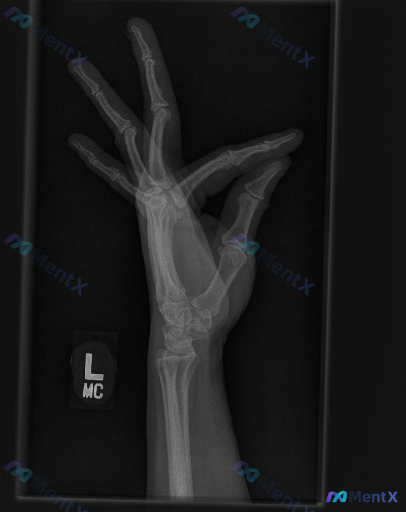

左手腕斜位X光片未见明确异常,但临床有症状时该怎么判断?

整理到一组左手及腕关节斜位X光片的影像观察资料,想和大家讨论下判读思路与后续临床处理逻辑。

- 骨骼完整性:舟骨整体轮廓可见,骨皮质连续;头状骨、月骨、三角骨、豌豆骨、钩骨等其他腕骨,以及第1-5掌骨、各指骨骨质连续性均良好,未见明确骨折线、嵌插或骨小梁紊乱表现。

- 关节对位:腕骨自然排列正常,关节间隙大致均匀;下尺桡关节对合尚可;掌指关节、指间关节间隙清晰对称,未见半脱位或脱位。

- 软组织与周围结构:未见明显弥漫性软组织肿胀,未见软组织内高密度异物或肌腱附着点病理性钙化。

- 退行性变与慢性改变:整体骨密度分布尚均匀,未见骨质疏松、局灶骨质破坏或溶骨性病变;关节边缘光滑,无骨赘形成,关节间隙无明显变窄或不对称;未见囊性变、骨软骨瘤或其他占位征象。

想问问大家:仅基于目前这组斜位X光片的表现,你对这个病例的核心判断会更倾向于哪一边?如果结合临床场景(比如有明确外伤史、局部疼痛或活动受限),后续思路又会怎么调整?